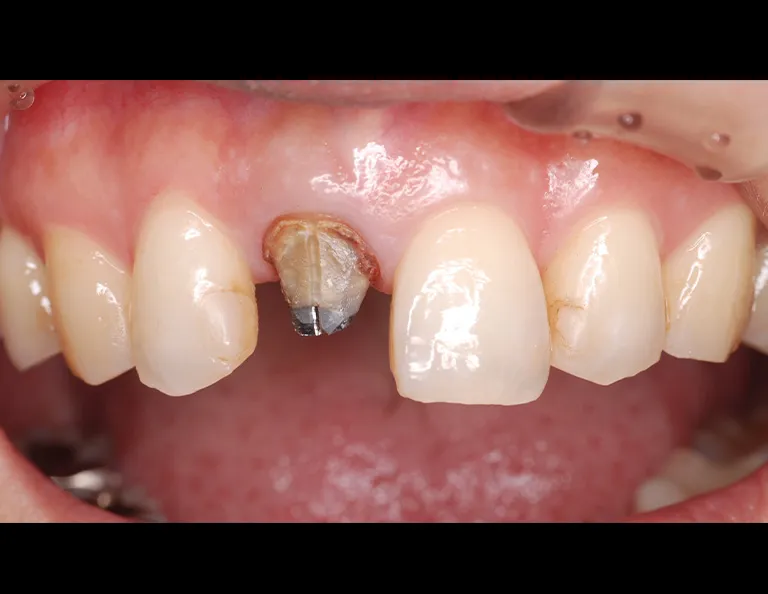

術前の状態です。右上中切歯の被せ物が合っていないことがわかります。また周りの歯の樹脂も劣化が認められます。

被せ物を外すとう蝕が認められました。

土台外すとさらに根管の中にもう蝕が認められました。

残っている歯の量が少ないため、根管治療後に部分矯正にて歯を引っ張り上げる(矯正的挺出)こととしました。

その際は表には仮歯をつけて見た目の確保を行います。

矯正的挺出が終わった状態です。歯とともに歯肉と骨も一緒に引っ張り上げられるので、

手術(歯冠長延長術)によって歯肉と骨を整形し、健康な歯の量を確保します。

歯冠長延長術を行ったところです。

その後土台を築造し、型取りを行います。

右上中切歯にセラミッククラウンを装着して、周りの歯の樹脂もやり替えを行いました。